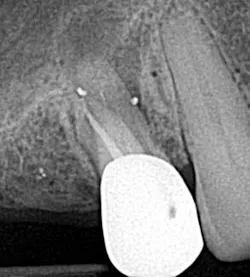

• File separation

Spin, spin, and snap! This is my least favorite endodontic complication (figure 3), which is why I wrote an entire article on it.